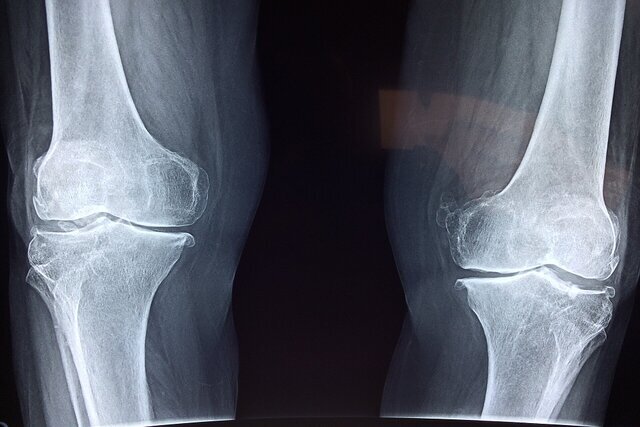

قلعهسفیدی درباره اینکه شکستگیهای ناشی از زمین خوردن بیشتر در کدام استخوانهای بدن رخ میدهد، یادآور شد: در زمینخوردن روی یخ، معمولاً فرد سعی میکند با دستها تعادل خود را حفظ کند و یا به پهلو و باسن میافتد. از همین رو شکستگی مچ دست(شکستگی رادیوس) در شرایطی که فرد سعی میکند با کف دست خود را نگه دارد، یکی از شایعترین انواع شکستگی است.

وی شکستگی لگن مخصوصا در سالمندان را نیز از دیگر شکستگیهای شایع برشمرد که به دلیل افتادن روی باسن و تراکم استخوان پایین رخ میدهد و ادامه داد: شکستگی مچ پا و ساق پا نیز به دلیل پیچخوردگی شدید یا گیرکردن پا، شکستگی بازو و شانه در اثر برخورد مستقیم با زمین و شکستگی ستون فقرات - که کمتر شایع بوده، اما خطرناک است- که معمولا در افتادنهای شدید رخ میدهد، از دیگر موارد شایع شکستگی در استخوانهای بدن است.